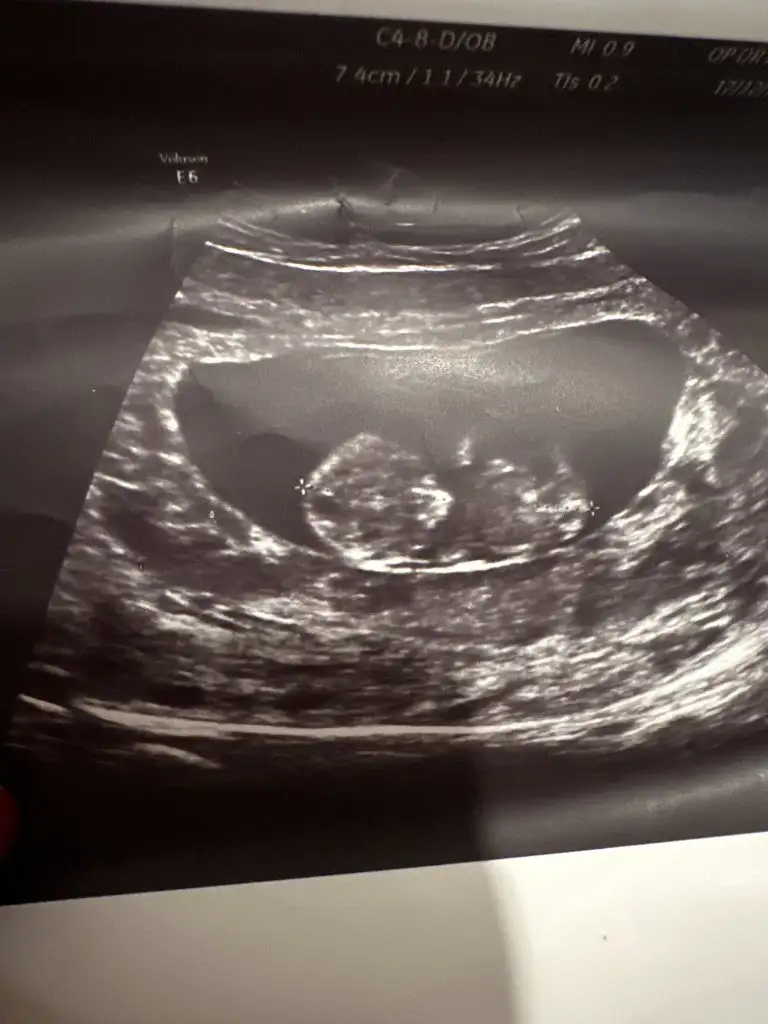

Bende tahmin alabilirmiyim

• IMG-20241114-WA0046.webp

IMG-20241114-WA0046.webp

21,4 KB · Görüntüleme: 63

• IMG-20241104-WA0021.webp

IMG-20241104-WA0021.webp

28,7 KB · Görüntüleme: 52

• IMG-20241104-WA0019.webp

IMG-20241104-WA0019.webp

26,1 KB · Görüntüleme: 48